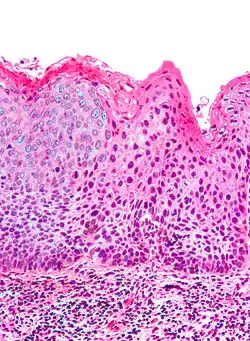

Micrograph of (classic) vulvar intraepithelial neoplasia III. H&E stain.

Medically speaking, the term denotes a squamous intraepithelial lesion of the vulva that shows dysplasia with varying degrees of atypia. The epithelial basement membrane is intact and the lesion is thus not invasive but has invasive potential.

Classic vulvar intraepithelial neoplasia: associated with developing into the warty and basaloid type carcinoma. This is associated with carcinogenic genotypes of HPV and/or HPV persistence factors such as cigarette smoking or immunocompromised states.